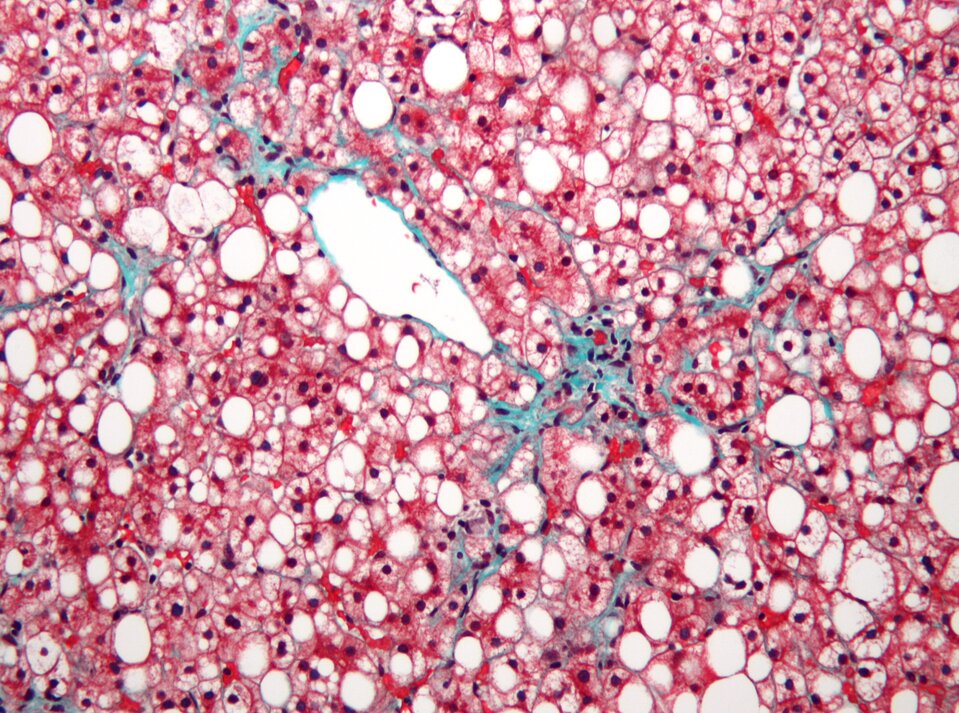

Próby wątrobowe to badania polegające na ocenie aktywności wybranych enzymów zawartych w komórkach wątroby, które w przypadku jej uszkodzenia są wyrzucane do krwi. Badania te polegają na ocenie aktywności tych enzymów oraz stężenia bilirubiny (produkt rozpadu hemoglobiny, barwnik żółci) we krwi. Pozwalają one wykryć uszkodzenie wątroby spowodowane cukrzycą czy nadużywaniem alkoholu i leków, a także zatrucia, np. grzybami. Są pomocne w diagnozowaniu przewlekłego stanu zapalnego wątroby wywołanego przez wirusy HBV i HCV (wirusy zapalenia wątroby typu B i C).

Badania diagnostyczne takie jak gastroskopia, kolonoskopia i USG jamy brzusznej odgrywają kluczową rolę w wczesnym wykrywaniu nieprawidłowości, umożliwiając diagnozowanie stanów zapalnych, nadżerek, polipów czy guzów. Regularne wykonywanie tych badań jest istotne w profilaktyce chorób nowotworowych przewodu pokarmowego, szczególnie raka żołądka i raka jelita grubego.